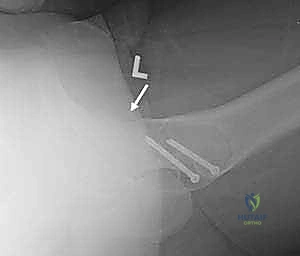

6. إصلاح الشفا الحقي (Labral Repair):

إذا كان الشفا الحقي ممزقاً (وهو أمر شائع جداً)، لا يتم استئصاله، بل يتم إعادة تثبيته وخياطته بعناية فائقة باستخدام خطاطيف جراحية صغيرة (Suture Anchors) تزرع في العظم. الحفاظ على الشفا ضروري جداً للحفاظ على صحة المفصل على المدى الطويل.

تُخاط الكبسولة بإحكام، ثم يُعاد عظم المدور الكبير إلى مكانه الأصلي ويُثبت باستخدام براغي طبية (Screws) مصنوعة من التيتانيوم لتأمين التئام العظم.